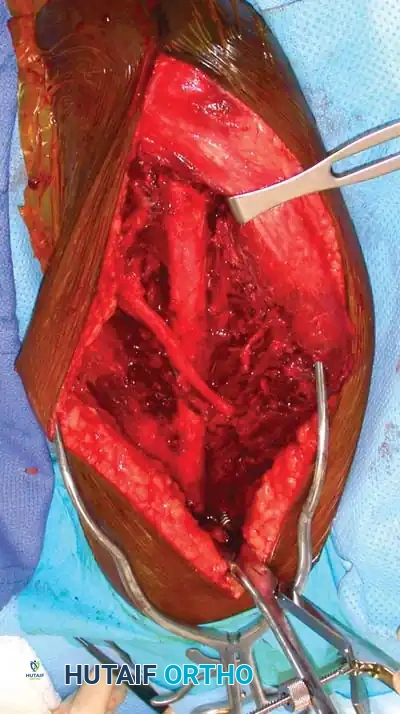

5. Deep Dissection and Radial Nerve Mobilization:

* Elevate the lateral head of the triceps off the lateral intermuscular septum.

* Identify the radial nerve and the profunda brachii artery as they pierce the lateral intermuscular septum to enter the anterior compartment.

* Carefully mobilize the radial nerve. Use vessel loops for gentle retraction. Never apply excessive traction to the nerve.

Fig. 54-33 D, Mobilization of the radial nerve.

6. Fracture Reduction and Fixation:

* Reflect the entire triceps muscle mass medially to expose the posterior humeral shaft.

* Reduce the fracture and apply the pre-selected LC-DCP. Ensure the radial nerve is completely free and not tethered beneath the plate.